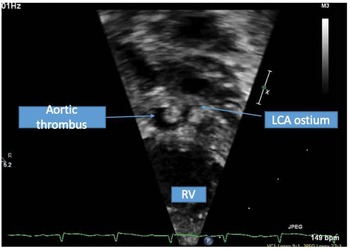

A term male infant was diagnosed postnatally at day 2 after being noted to have tachypnoea which prompted a cardiology workup and was noted to have hypoplastic left heart syndrome with severe mitral and aortic valve stenosis. At 1 week, he underwent Norwood procedure with Sano shunt placement. The Norwood was done with incising down the ascending aorta with side-to-side anastomosis with continuous monofilament sutures with knots on the outside. He had uncomplicated post-operative course and was extubated on post-operative day #5. His initial post-op echo showed unrestrictive atrial septal defect, mild tricuspid regurgitation, patent aortic arch, and Sano shunt with patent Damus–Kaye–Stansel anastomosis with no thrombus noted (Fig 1). On post-operative day #9, he was noted to have sudden onset clinical change after a routine chest physiotherapy and was noted to have sudden onset of bradycardia and hypotension, elevated ST segments with low cerebral and somatic Near Infra-Red Spectroscopy, and elevated blood lactate. A 15 Lead electrocardiogram showed ST elevation (Fig 2). His native aortic root measured around 5 mm and the ascending aorta was 4 mm. The sinotubular junction of the native aortic root measured around 4 mm. An echocardiogram showed a large thrombus (around 5 × 3.5 mm) in his aortic root occluding blood flow into the left main coronary artery (Fig 3a). His labs showed elevated troponins with an initial value of around 14 ng/ml (reference range 0–0.39 ng/ml) which peaked to around 83 ng/ml within 24 hours, with resolution over a week. The patient was intubated, started on low dose epinephrine, and sedated and paralyzed with improved haemodynamics. Haematology was consulted and the patient was started on low dose tissue plasminogen activator at around 0.06 mg/kg/hour, which was titrated to around 0.08 mg/kg/hour based on clot size. Repeat echocardiogram imaging over the next few days revealed decreasing clot size and eventual resolution of thrombus with adequate perfusion of coronary arteries after 72 hours of thrombolysis treatment (Fig 3b).

Figure 1. Short axis of the aortic root with echogenic mass noted in native aortic root consistent with thrombus.